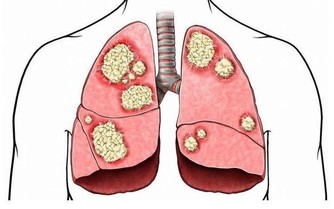

食物消化後的殘渣也要通過腸道排泄出去,如果這些垃圾堆積在體內不及時排出去,就會產生很多有害物質,引起腹漲、腹痛,甚至引起腸道擴張、誘發腫瘤。

4、免疫防禦

人體60%-80%的淋巴細胞都在腸道裡,它們和腸道黏膜、粘液一起保護著我們的健康,把進入人體的有害物質消滅掉。